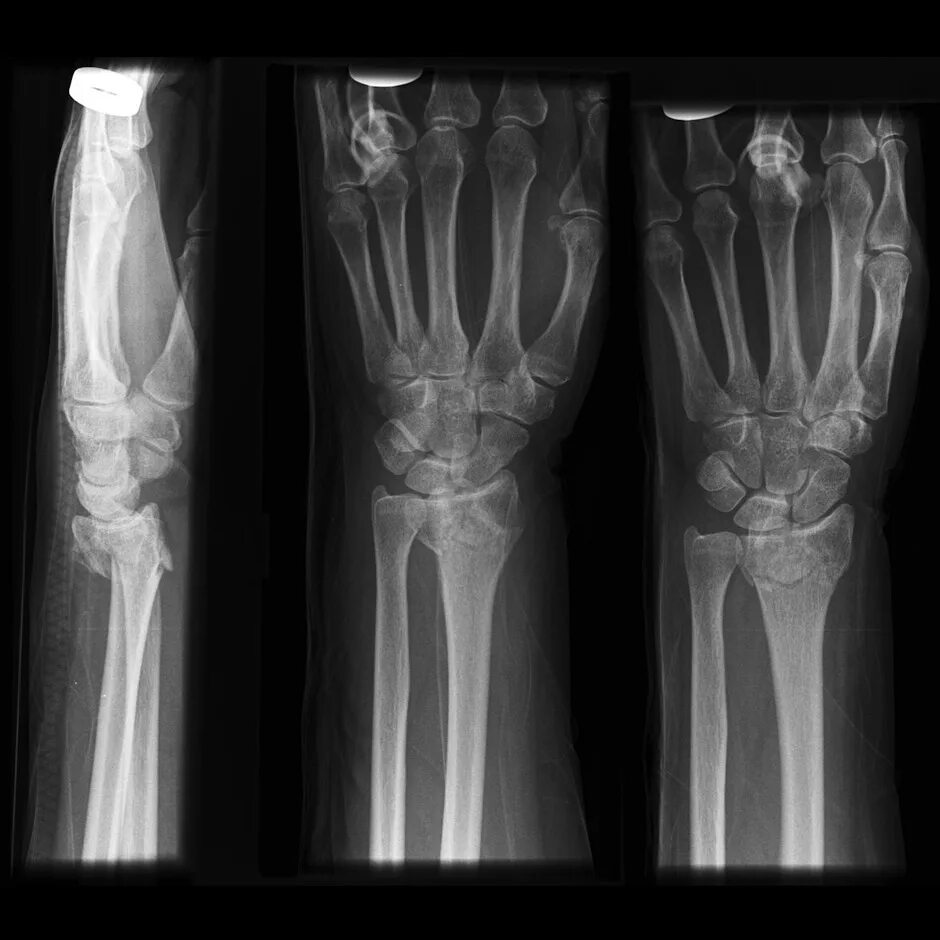

Смещение лучезапястной кости